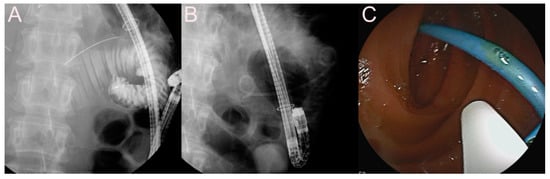

2.2. Stent for EUS-Guided Bile Duct (BD) Drainage

2.2.1. Use of the Plastic Stent

2.2.2. Use of the SEMS

2.2.3. Use of the LAMS